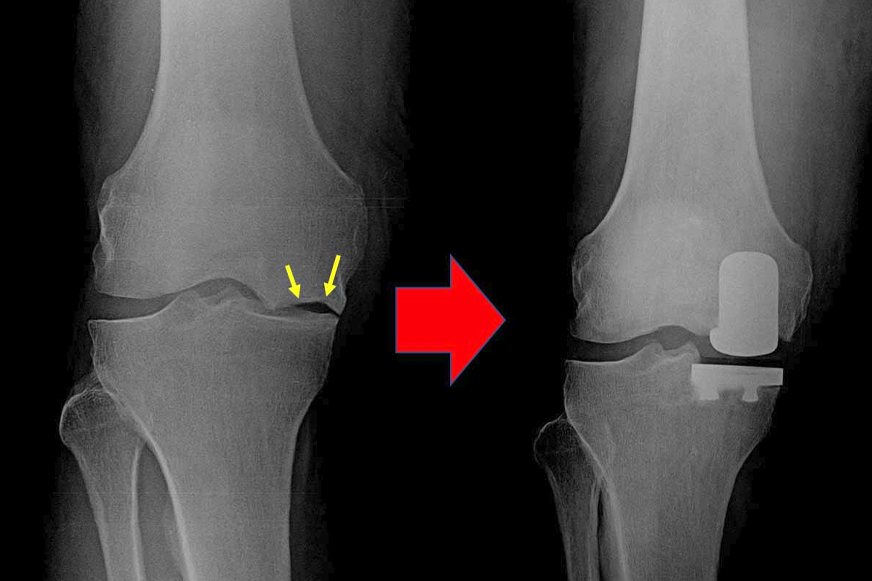

Your doctor may recommend knee replacement surgery to you after other non-surgical methods fail to provide relief. But not all such issues necessitate complete knee joint replacement. If damage is not widespread and limited only to one component of the knee joint, then healthy joint components are preserved with the partial knee replacement surgery.

Partial knee replacement (PKR) is also called unicompartmental knee replacement because in this surgical procedure only the damaged portion of the knee joint is replaced with an artificial implant.

Early-stage knee damage can be stopped from progressing and can be effectively reversed with non-surgical conservative treatment options such as medications, supplementation, physiotherapy, weight management, and injections. If these treatments fail or are no longer effective for relieving pain, knee replacement may be recommended. Your orthopaedic surgeon may consider partial knee replacement if:

The surgery is usually completed between one and two hours. The damaged bone and cartilage are taken out during the procedure, and bone cement or press-fit techniques are used to fix the implants. Before closing, the alignment and stability of the joint are checked.